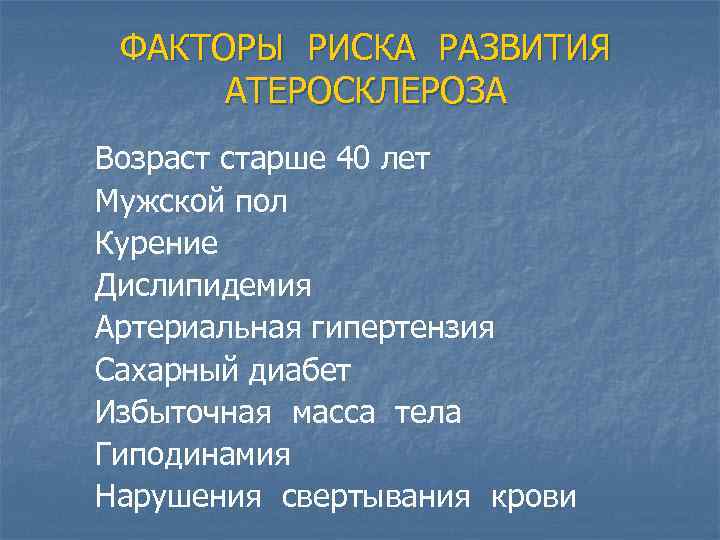

ФАКТОРЫ РИСКА РАЗВИТИЯ АТЕРОСКЛЕРОЗА Возраст старше 40 лет Мужской пол Курение Дислипидемия Артериальная гипертензия Сахарный диабет Избыточная масса тела Гиподинамия Нарушения свертывания крови